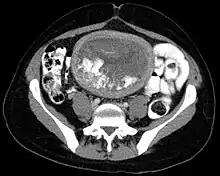

Hydatidiform mole on CT, axial view

The diagnosis is strongly suggested by ultrasound (sonogram), but definitive diagnosis requires histopathological examination. On ultrasound, the mole resembles a bunch of grapes ("cluster of grapes" or "honeycombed uterus" or "snow-storm").[14] There is increased trophoblast proliferation and enlarging of the chorionic villi, and angiogenesis in the trophoblasts is impaired.[15]